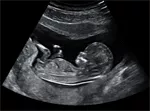

- the spread of ultrasound screening since the 1980s, making it possible to determine the sex of a fetus before birth;